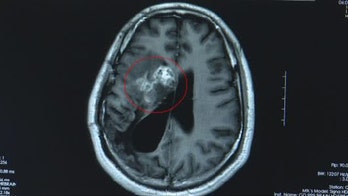

Surgery November 5, 2019 Man has 12-centimeter parasitic worm removed from brain after years of numbness, blackouts The parasite had allegedly been living in his brain for 15 years.